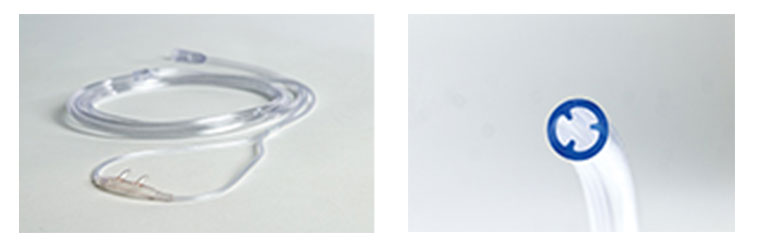

アトム酸素鼻孔カニューラ OX-20 28医用ディスポーザブル製品製品情報アトムメディカル株式会社。

アトム酸素鼻孔カニューラ。

最安値 1個あたり550円 リタエアー リタアクア専用 吸入チューブ 鼻用カニューレ×10個 レビューでイズミオ1本もらえる送料無料ポイント3倍。

付属パーツの使い方水素吸入器のレンタルはリタエア。

水素吸入器リタエアーの鼻カニューレ カニューラ の上下の向きや装着方法水素吸入器レンタルのリタエア。

アトム酸素鼻孔カニューラ OX-20 28医用ディスポーザブル製品製品情報アトムメディカル株式会社。

楽天市場 <本日、P2倍!!> \2個購入で50円OFF 送料無料 アトム 酸素鼻孔カニューラ 酸素カニューラ 酸素カニューレ カニューレ カニューラ酸素管 酸素チューブ チューブ チューブ O2 HOT 在宅酸素 水素 吸入 吸引 個別梱包品 : 美沢メディカルサービス。